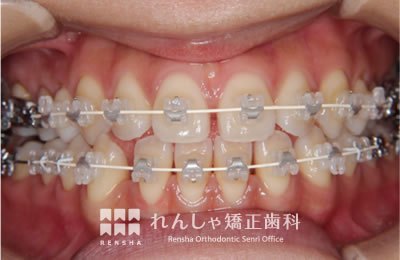

中高生

永久歯列はほぼ完成してしますが、歯列を側方だけでなく後方へも拡大し、埋まっていた右上奥歯を引っ張り出しています。

治療中

→

| 主訴 | 埋まったままでてこない歯がある |

|---|---|

| 診断名 | Angle Class II 小臼歯の埋伏と叢生を伴う上顎前突 |

| 初診時年齢 | 13歳5か月 |

| 装置名 | マルチブラケット装置 |

| 抜歯非抜歯 | 非抜歯 |

| 治療期間 | 2年3か月 |

| 費用の目安 | 約82万円+消費税(検査料金、都度の処置費用等も合わせた総額) |

| リスク副作用 | 歯の移動に伴う軽微な歯根吸収、歯槽骨吸収、歯肉退縮(本症例では軽度の歯根吸収を認めた)、矯正器具装着中のカリエスリスク増大(本症例ではカリエス発生無し) |